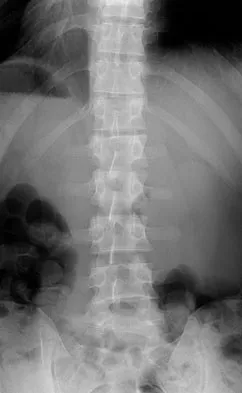

Which of the following choices best describes the fracture pattern shown in Figures 2a through 2c?

Explanation

The fracture pattern shown in the radiographs is a fracture of the posterior column. The only line interrupted on the AP pelvis is the ilioischial line. The obturator oblique view shows that the iliopectineal line is intact as is the outline of the posterior wall. The iliac oblique view shows an interruption of the ilioischial line and an intact anterior wall. Therefore, this fracture is a fracture of the posterior column. Letournel E, Judet R: Fractures of the Acetabulum, ed 2. Berlin, Germany, Springer Verlag, 1993.